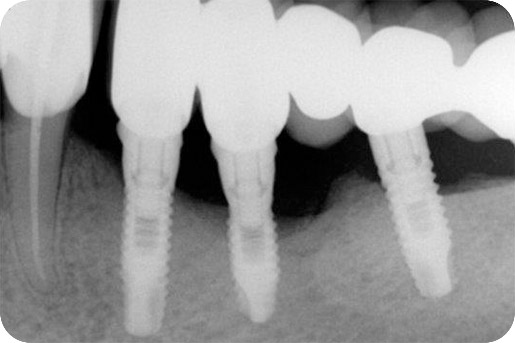

Figure 2

radiograph illustrating peri-implantitis (courtesy of Dr. Liran Levin)